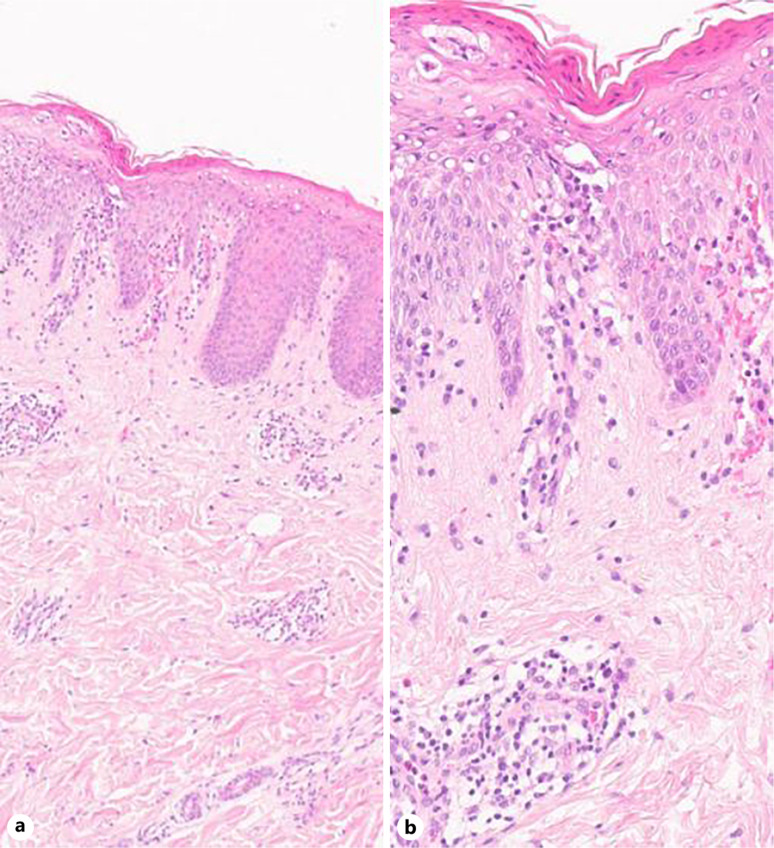

简介:苔藓样糠疹(PL)是一种炎症性皮肤病,包括急性(PLEVA)和慢性(PLC)亚型,它们具有重叠的临床和组织病理学特征。标准的治疗方式包括口服抗生素、光疗和免疫抑制剂。Dupilumab是一种被批准用于特应性皮炎的IL-4Rα拮抗剂,已被用于各种炎症性皮肤状况。然而,它在PLC管理中的作用仍然缺乏文档记录。病例介绍:我们报告一例PLC成功治疗杜匹单抗。患者有白癜风病史,既往接受过单苯酮脱色治疗。由于担心潜在的色素变化,dupilumab开始时的负荷剂量为600 mg,随后是300 mg,每两周服用一次。治疗3个月后,PLC病变和瘙痒明显改善,仅残留红斑斑块。出乎意料的是,自发皮肤色素沉着发生,与先前报道的使用杜匹单抗后白癜风加重形成对比。患者恢复单苯酮治疗,未出现PLC复发或瘙痒加重。结论:该病例强调了dupilumab作为PLC有效治疗的潜力,以及它在促进既往白癜风患者皮肤色素沉着方面的可能作用。这些发现表明2型炎症与PLC发病机制之间存在潜在联系,值得进一步研究。Dupilumab可能是难治性PLC的一种有前景的治疗选择。

Introduction: Pityriasis lichenoides (PL) is an inflammatory skin disorder encompassing both acute (PLEVA) and chronic (PLC) subtypes, which share overlapping clinical and histopathological features. Standard treatment modalities include oral antibiotics, phototherapy, and immunosuppressive agents. Dupilumab, an IL-4Rα antagonist approved for atopic dermatitis, has been used off-label for various inflammatory skin conditions. However, its role in PLC management remains poorly documented.